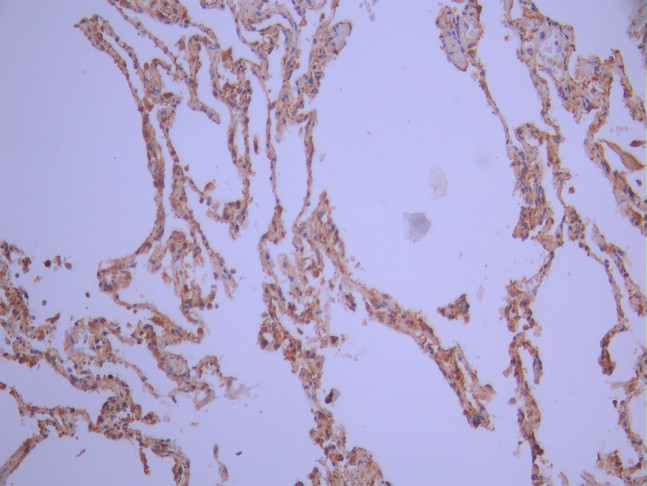

IHC image of CSB-RA174440A0HU diluted at 1:100 and staining in paraffin-embedded human lung tissue performed on a Leica BondTM system. After dewaxing and hydration, antigen retrieval was mediated by high pressure in a citrate buffer (pH 6.0). Section was blocked with 10% normal goat serum 30min at RT. Then primary antibody (1% BSA) was incubated at 4°C overnight. The primary is detected by a Goat anti-rabbit polymer IgG labeled by HRP and visualized using 0.05% DAB.